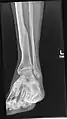

Coronal cross-section through the right ankle showing the lateral malleolus (right) and medial malleolus (left)

A malleolus is the bony prominence on each side of the human ankle.

Each leg is supported by two bones, the tibia on the inner side (medial) of the leg and the fibula on the outer side (lateral) of the leg. The medial malleolus is the prominence on the inner side of the ankle, formed by the lower end of the tibia. The lateral malleolus is the prominence on the outer side of the ankle, formed by the lower end of the fibula.